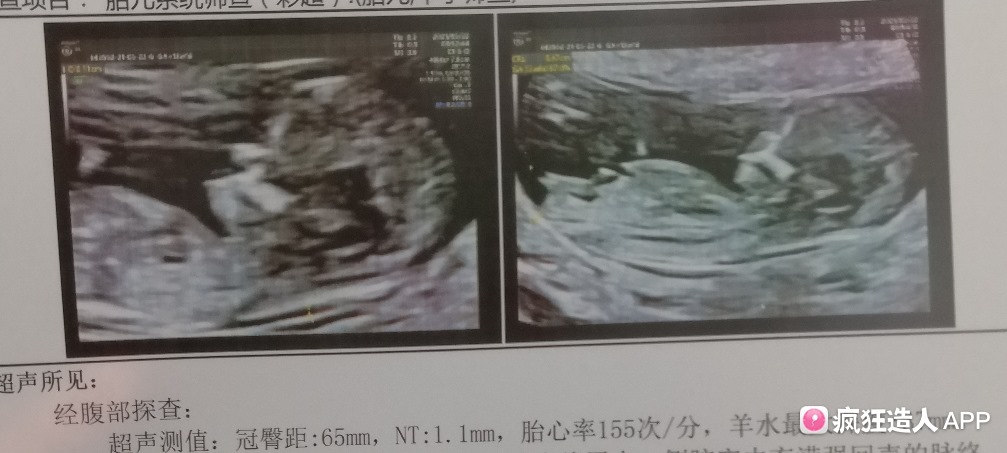

12周nt特点NT值是什么?

NT检查大部分的妈妈都是在孕期12周左右做的,这时候宝宝的性征已经发育明显,如果能看到超声的图片,其实是可以看出男女的,我们在图片上可以看到具有性征的一些身体特点,男孩的特征点与身体呈45度角,还多一些,而女孩儿的特征点几乎和躯体平行。还有就是如果是宝,位置会微微,后背脊柱成圆弧状,因为要留空间发育,相反,女宝宝后背脊柱就相对就平一些。

除了看图,很多家长都说NT值大于1.5的宝宝就是男孩,而小于1.5就是女孩。